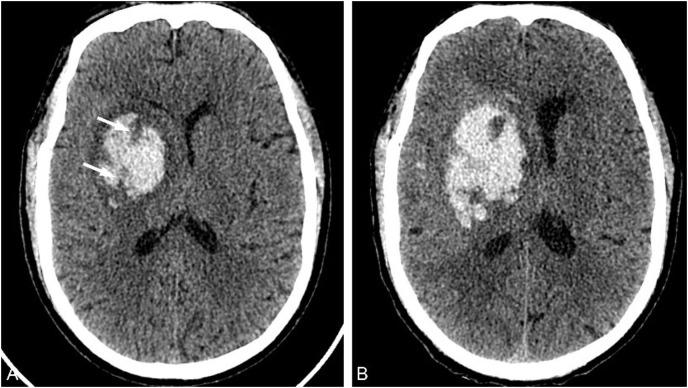

基于 CT 图像预测高血压性脑出血扩大的研究进展:综述。

Research advances in predicting the expansion of hypertensive intracerebral hemorrhage based on CT images: an overview.

Hematoma expansion (HE) is an important risk factor for death or poor prognosis in patients with hypertensive intracerebral hemorrhage (HICH). Accurately predicting the risk of HE in patients with HICH is of great clinical significance for timely intervention and improving patient prognosis. Many imaging signs reported in literatures showed the important clinical value for predicting HE. In recent years, the development of radiomics and artificial intelligence has provided new methods for HE prediction with high accuracy. Therefore, this article reviews the latest research progress in CT imaging, radiomics, and artificial intelligence of HE, in order to help identify high-risk patients for HE in clinical practice.

血肿扩大(HE)是高血压性脑出血(HICH)患者死亡或预后不良的重要危险因素。准确预测 HICH 患者发生 HE 的风险,对于及时干预和改善患者预后具有重要的临床意义。文献中报道的许多影像学征象均显示出对预测 HE 的重要临床价值。近年来,影像组学和人工智能的发展为 HE 预测提供了高精度的新方法。因此,本文综述了 HE 的 CT 影像学、影像组学和人工智能的最新研究进展,以期有助于在临床实践中识别出 HE 的高危患者。